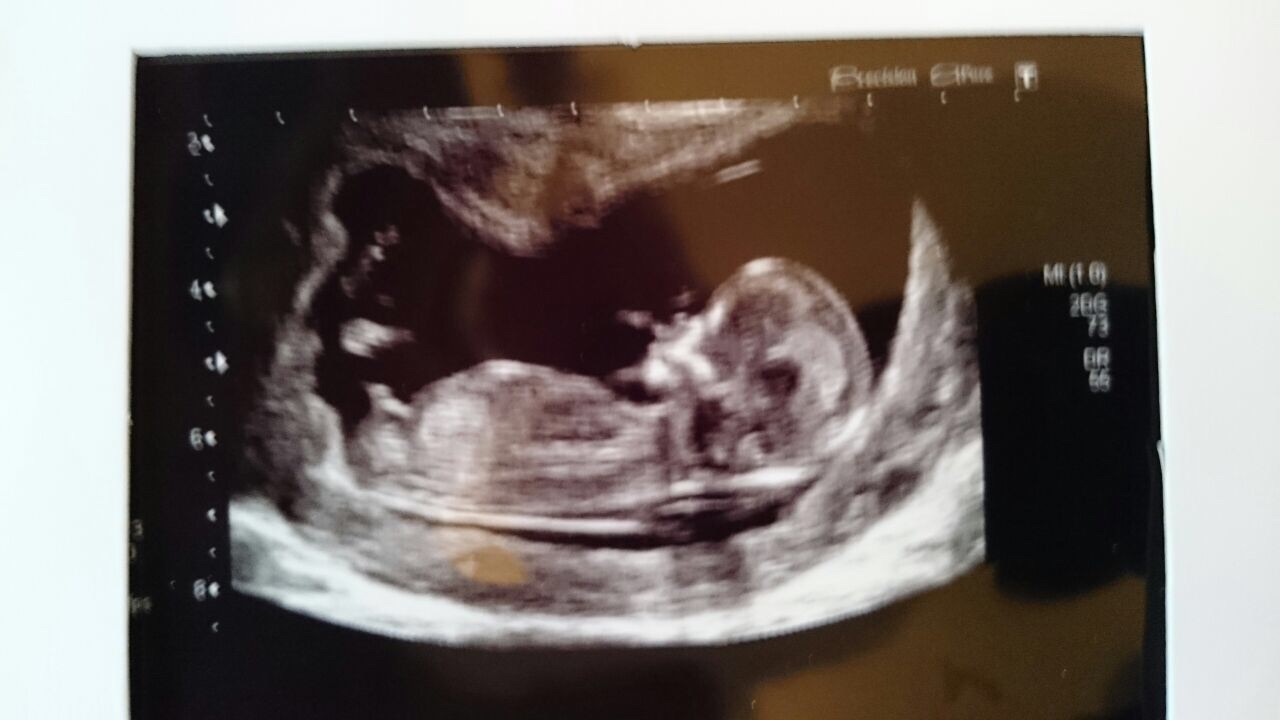

This is my sister in laws scan at 13+2 she would love your guesses Attachment 25531